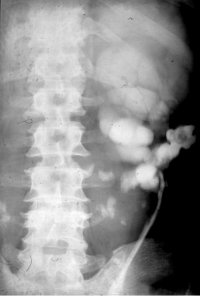

Der Patient kam mit Zeichen eines schweren, fieberhaften Harnwegsinfektes in unsere Behandlung. Die Diagnostik mit Sonographie und Ausscheidungsurogramm sowie Angiographie ergab eine ausgedehnte Harnsteinbildung beiderseits, wobei es im linken Nierenanteil zu Harnabflussbehinderungen gekommen war. Die Abbildungen zeigen die diagnostischen Maßnahmen. Der linke Nierenanteil wurde wegen erheblichen pyonephrotischem Umbau entfernt.